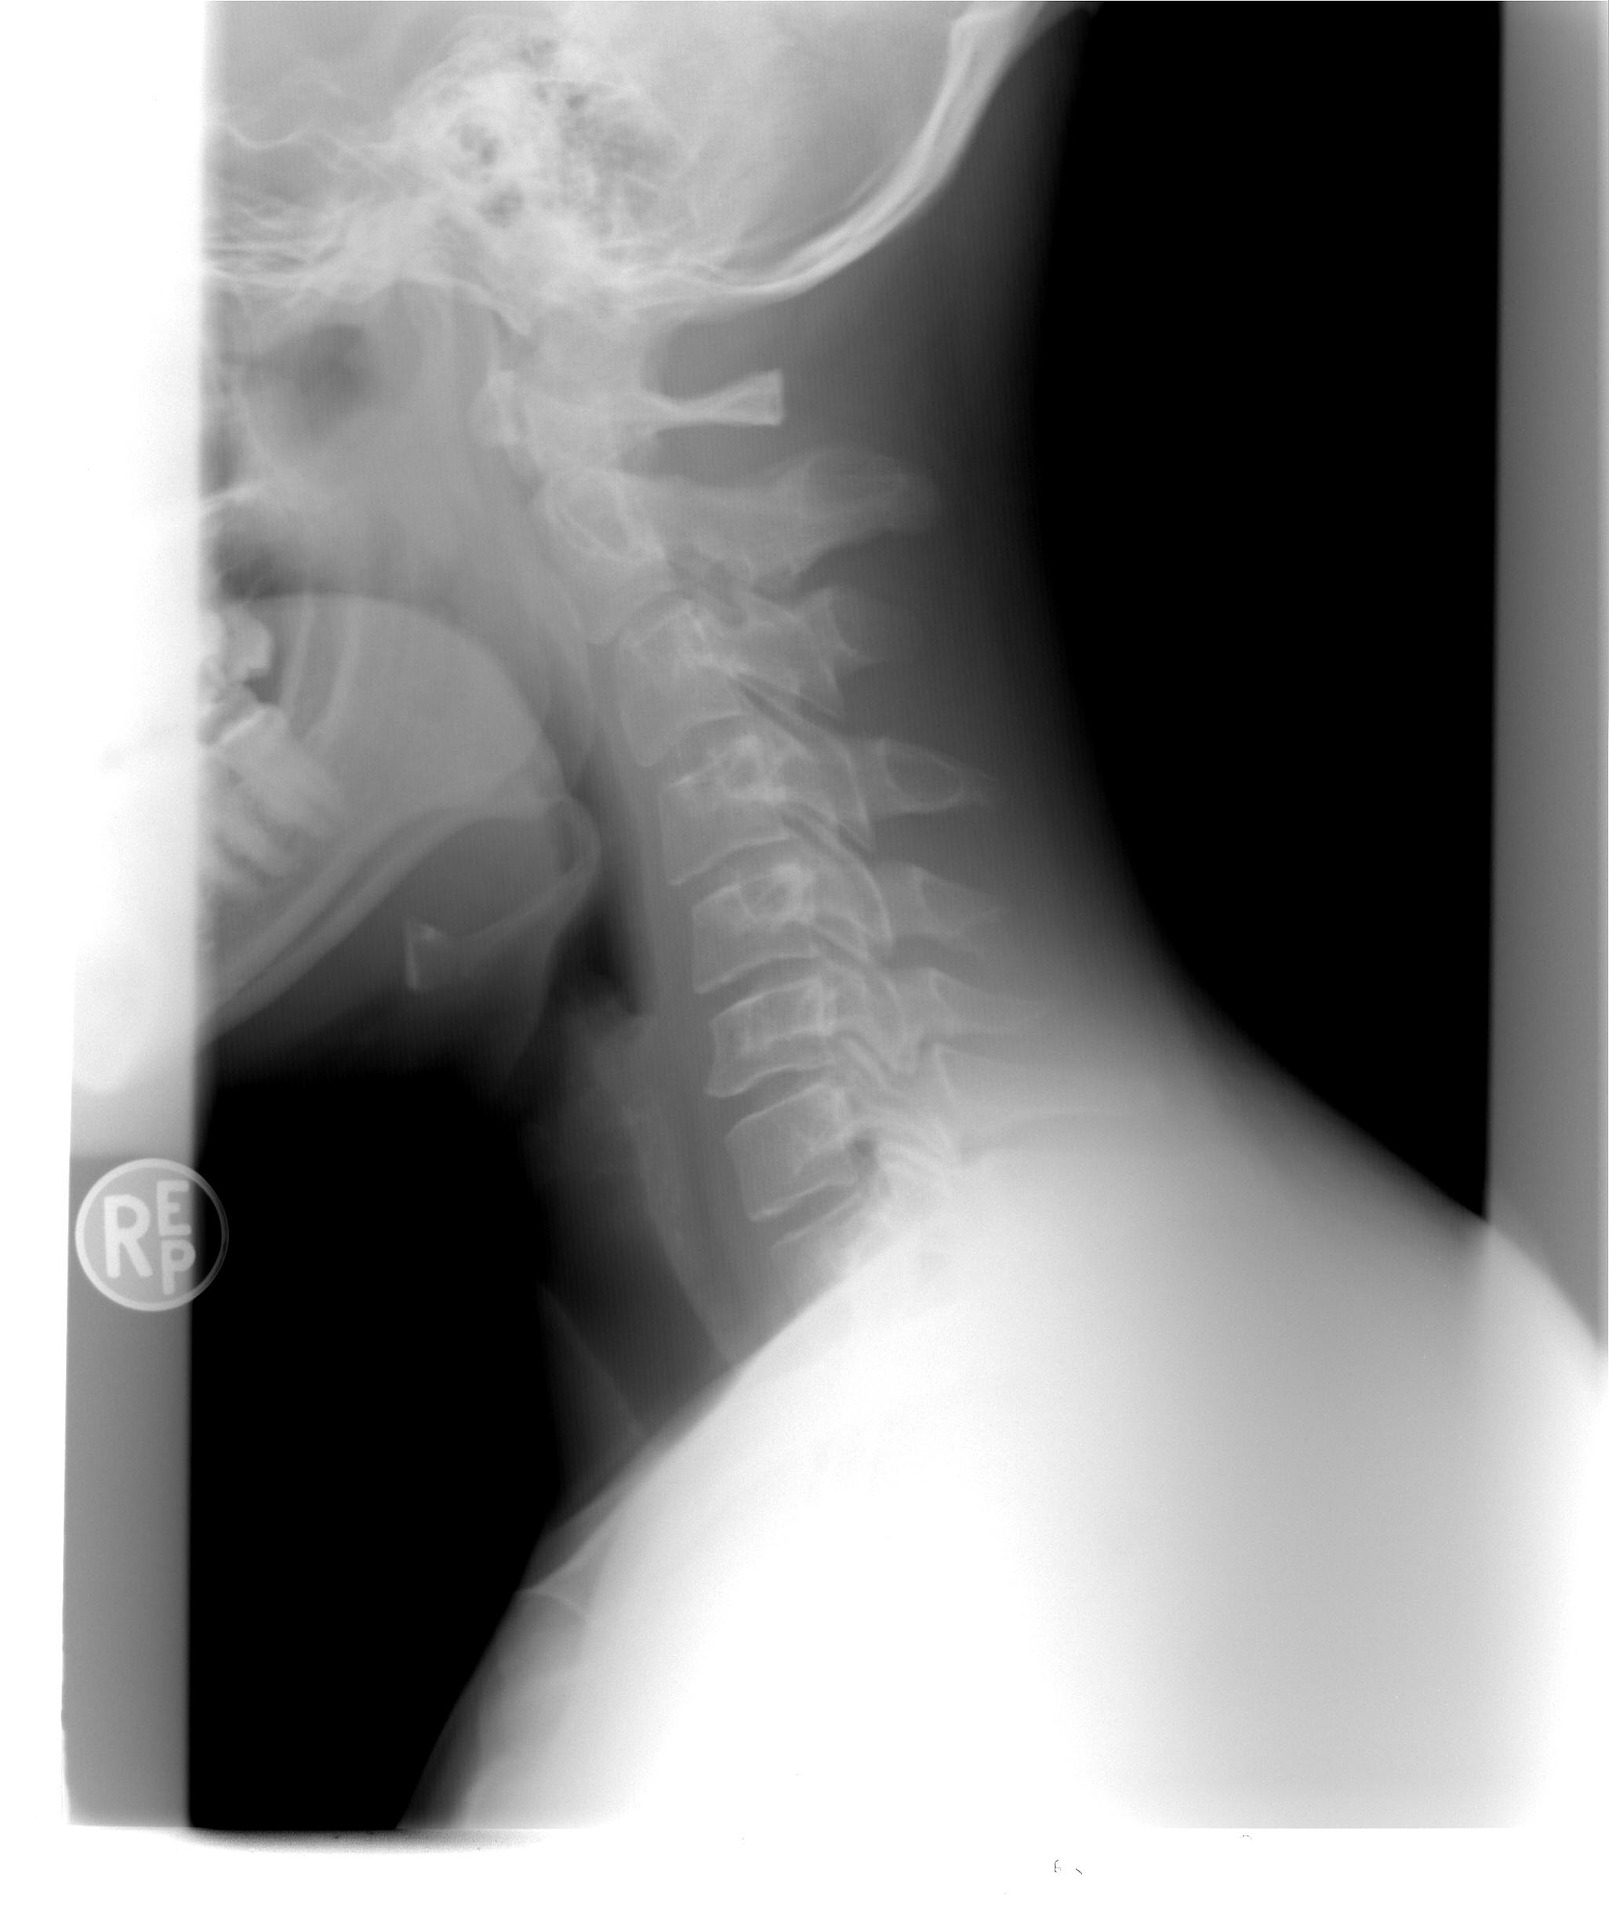

Odpowiednia stymulacja tych miejsc pozwala nie tylko pozbyć się bólu, ale też poprawiać stan zdrowia człowieka. Najwięcej punktów, które poddaje się stymulacji, jest zlokalizowanych na stopach i dłoniach, ale też na uszach. Poznaj miejsca, których uciskanie pozwala szybko pozbyć się nie tylko bólu głowy, ale także ramion i szyi!

Pierwsze miejsce, które należy naciskać, znajdziesz pomiędzy kciukiem a palcem wskazującym. Nie może być to zbyt intensywny dotyk. Najlepszym rozwiązaniem jest delikatny masaż okrężnymi ruchami, trwający parę minut. Ból szyi, głowy czy ramion powinien zniknąć po stronie, po której wykonywano masaż.

Kolejne miejsce znajduje się na ramieniu, w połowie odległości między łokciem a barkiem. Punkt ten jest bolesny nawet przy małym nacisku. Należy masować go okrężnymi ruchami przez kilka minut.